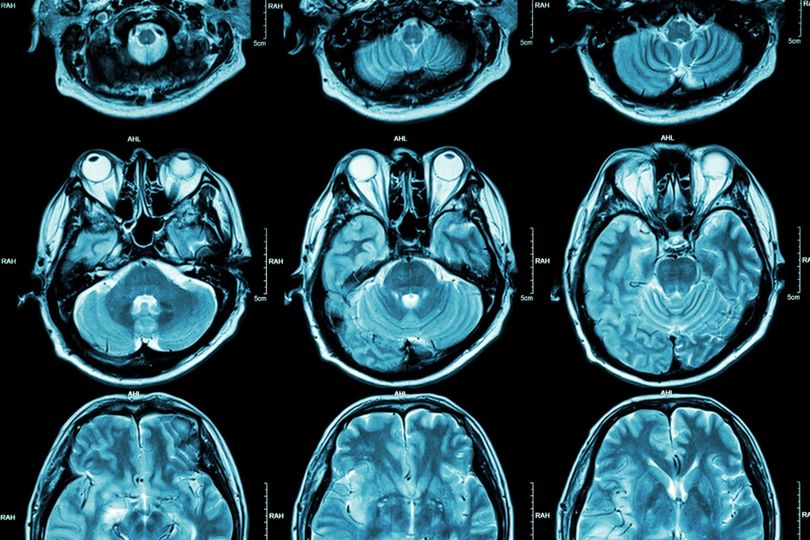

Το πολυδιάστατο σύμπαν που κρύβεται στον ανθρώπινο εγκέφαλο

Ο άνθρωπος, σύμφωνα με τον Άλμπερτ Αϊνστάιν, έχει την ικανότητα να κατανοεί τον κόσμο σε τέσσερις διαστάσεις, τρεις του χώρου, δηλαδή μήκος, πλάτος, ύψος, και μία του χρόνου. Τουλάχιστον έτσι πιστεύαμε μέχρι σήμερα. Ωστόσο, σύμφωνα με νέα επιστημονική έρευνα, οι δομές του εγκεφάλου μας είναι πολύ περισσότερο πολύπλοκες και αντιλαμβάνονται το περιβάλλον και τον κόσμο με έως και 11 διαστάσεις.

Στη σχετική ανακοίνωση στο περιοδικό υπολογιστικής νευροεπιστήμης «Frontiers in Computational Neuroscience» οι επιστήμονες ανακοίνωσαν ότι αποκάλυψαν ένα σύμπαν πολυδιάστατων γεωμετρικών δομών μέσα στα δίκτυα του εγκεφάλου.

Αυτές οι δομές πολλών διαστάσεων εμφανίζονται όταν κάθε νευρώνας συνδέεται με άλλους με τέτοιο τρόπο που δημιουργείται ένα ιδιόμορφο γεωμετρικό αντικείμενο. Όσο περισσότεροι νευρώνες εμπλέκονται μαζί στην ίδια «κλίκα» τόσο αυξάνονται οι διαστάσεις αυτού του γεωμετρικού αντικειμένου.

«Βρήκαμε έναν κόσμο που ποτέ δεν είχαμε φανταστεί. Υπάρχουν δεκάδες εκατομμύρια τέτοια αντικείμενα ακόμη και σε μια μικρή κουκκίδα του εγκεφάλου, έχοντας έως επτά διαστάσεις. Σε μερικά εγκεφαλικά δίκτυα, βρήκαμε δομές ακόμη και με 11 διαστάσεις», δήλωσε ο καθηγητής Μάρκραμ.